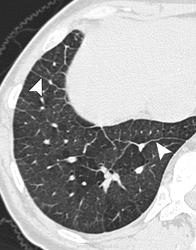

Легочная вено - окклюзионная болезнь (ЛВОБ)- редкое заболевание не установленной этиологии, при котором развитие и прогрессирование ЛГ связано с поражением мелких легочных вен и венул, в том числе тромботического характера.

Ранее ЛВОБ рассматривалась как подтип первичной легочной гипертензии (ПЛГ), однако с учетом вероятных различий в патогенезе ЛВОБ и лечении ПЛГ, в 1998г. ЛВОБ была включена в категорию легочной венозной гипертензии наряду с заболеваниями левых отделов сердца, компрессией легочных вен, фиброзирующим медиастинитом. В 2003г. на 3-м Мировом симпозиуме по ЛГ в Венеции (Италия) на основании сходных патоморфологических проявлений, клинической картины и возможного развития отека легких при назначении простагландинов ЛВОБ и легочный капиллярный гемангиоматоз- доброкачественное неметастазирующее сосудистое образование, приводящее к развитию ЛГ- были объединены в один подтип клинического класса легочной артериальной гипертензии.